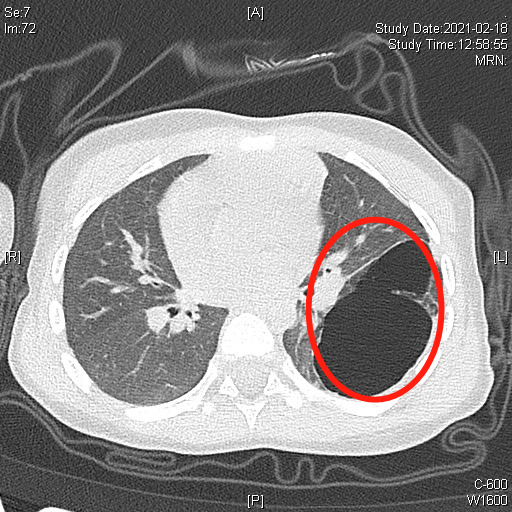

晗晗出生后最初没有明显症状,近期,她突然咳嗽咳痰加剧,在当地医院检查肺部CT发现左肺囊性病灶较刚出生时增大了不少,有3.8×6.4×5.6cm,相当于一个鸡蛋大小。

▲CT显示左侧胸腔巨大病灶

由于晗晗的胸腔空间狭小,小儿支气管血管发育较细小,分离困难,病灶跨叶生长,在保证手术切除范围的同时还要尽可能多保留患儿正在生长发育的肺组织,手术难度极大。